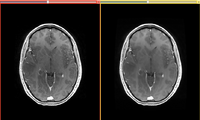

GradientAnisotropicDiffusion-Before-After-2011-08-11.png